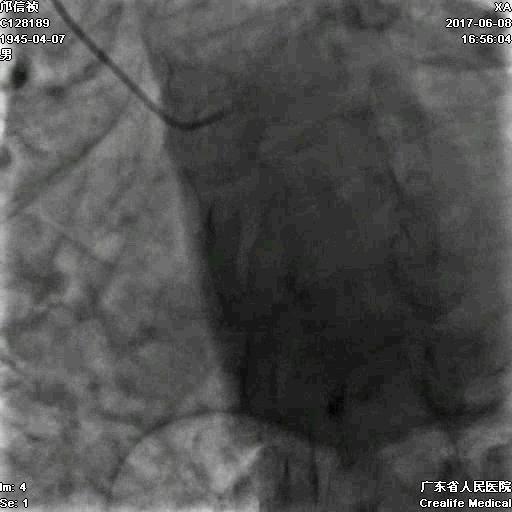

冠脉造影

基本资料

Syntax score 37.5